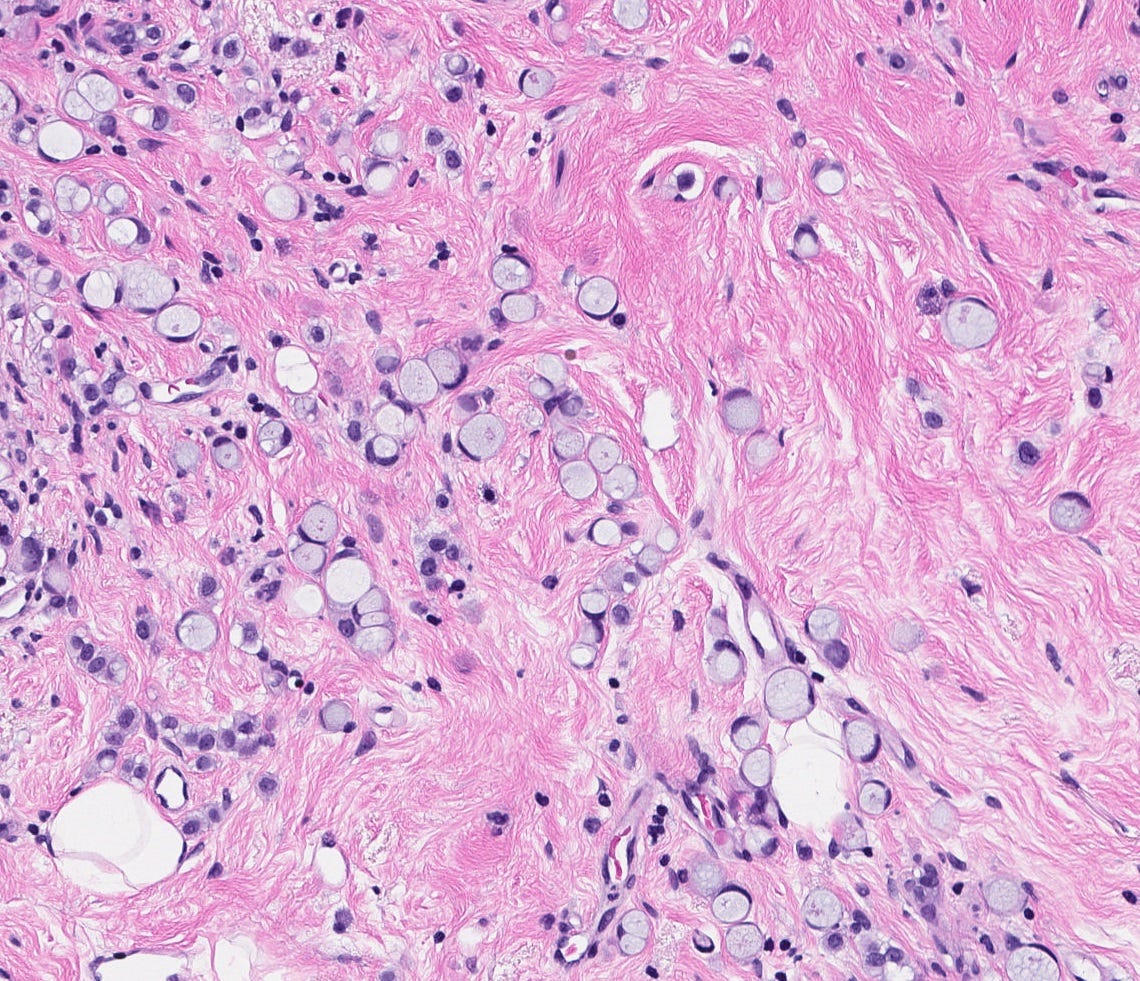

Precursor of classic lobular carcinoma - florid lobular carcinoma in situ

Florid LCIS is a rare (< 5% of LCIS) nonclassical or variant form of lobular carcinoma in situ in which acini and ducts are markedly distended with little to no intervening stroma. It may have a mass-like architecture and includes cells with cytologic features of classic LCIS (type A or type B cells) with or without comedonecrosis and calcifications. Most cases are associated with classic LCIS or atypical lobular hyperplasia (ALH).

Florid LCIS has features of a high risk precursor lesion of invasive carcinoma including a higher upgrade rate, increased association with invasive carcinoma and more genetic complexity compared to classic LCIS.

In contrast to classic LCIS, complete surgical excision of florid LCIS is recommended.

Florid lobular carcinoma in situ - microscopic images